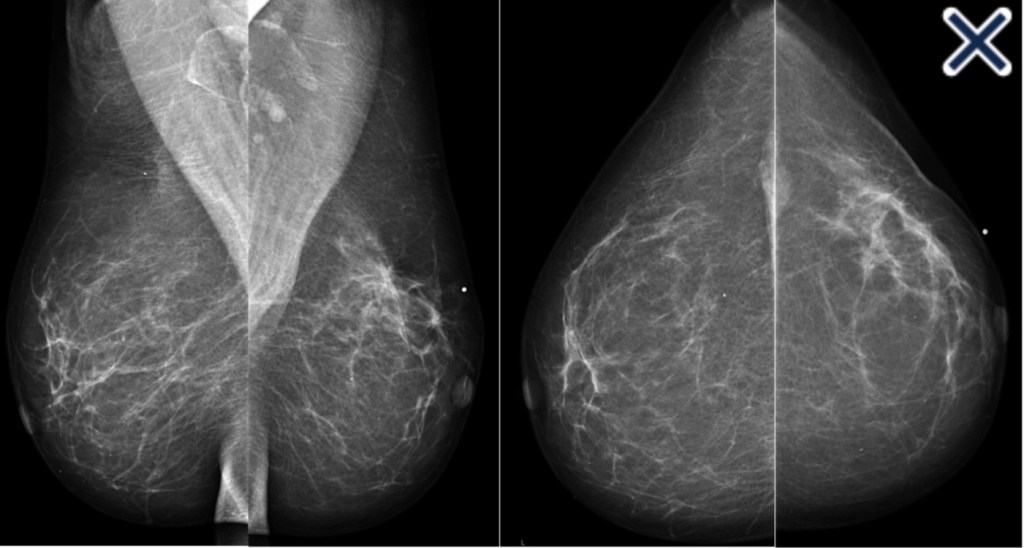

- Has a mammographic appearance of:

- Diffuse architectural distortion:

- Usually involving a large area, often larger than a lobe:

- With no central tumor mass and no calcifications

- It sometimes has the appearance of a “spider’s web” as shown in Image

- The diffusely infiltrating cancer:

- Forms concave contours with the surrounding fat in a manner similar to normal fibroglandular tissue (Images Above)